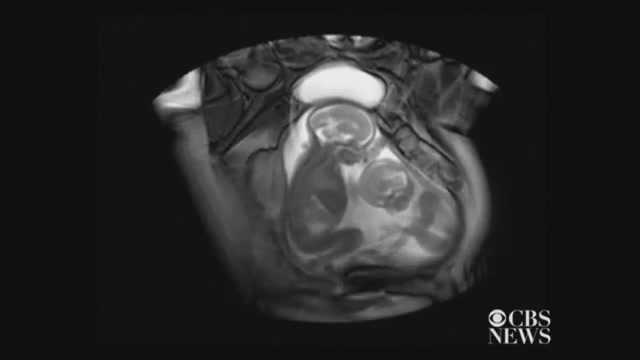

(VTC News) - Các nhà nghiên cứu tại London, Anh đã ghi lại được đoạn clip “đá nhau giành chỗ” rất thú vị của một cặp thai đôi qua hình ảnh siêu âm.